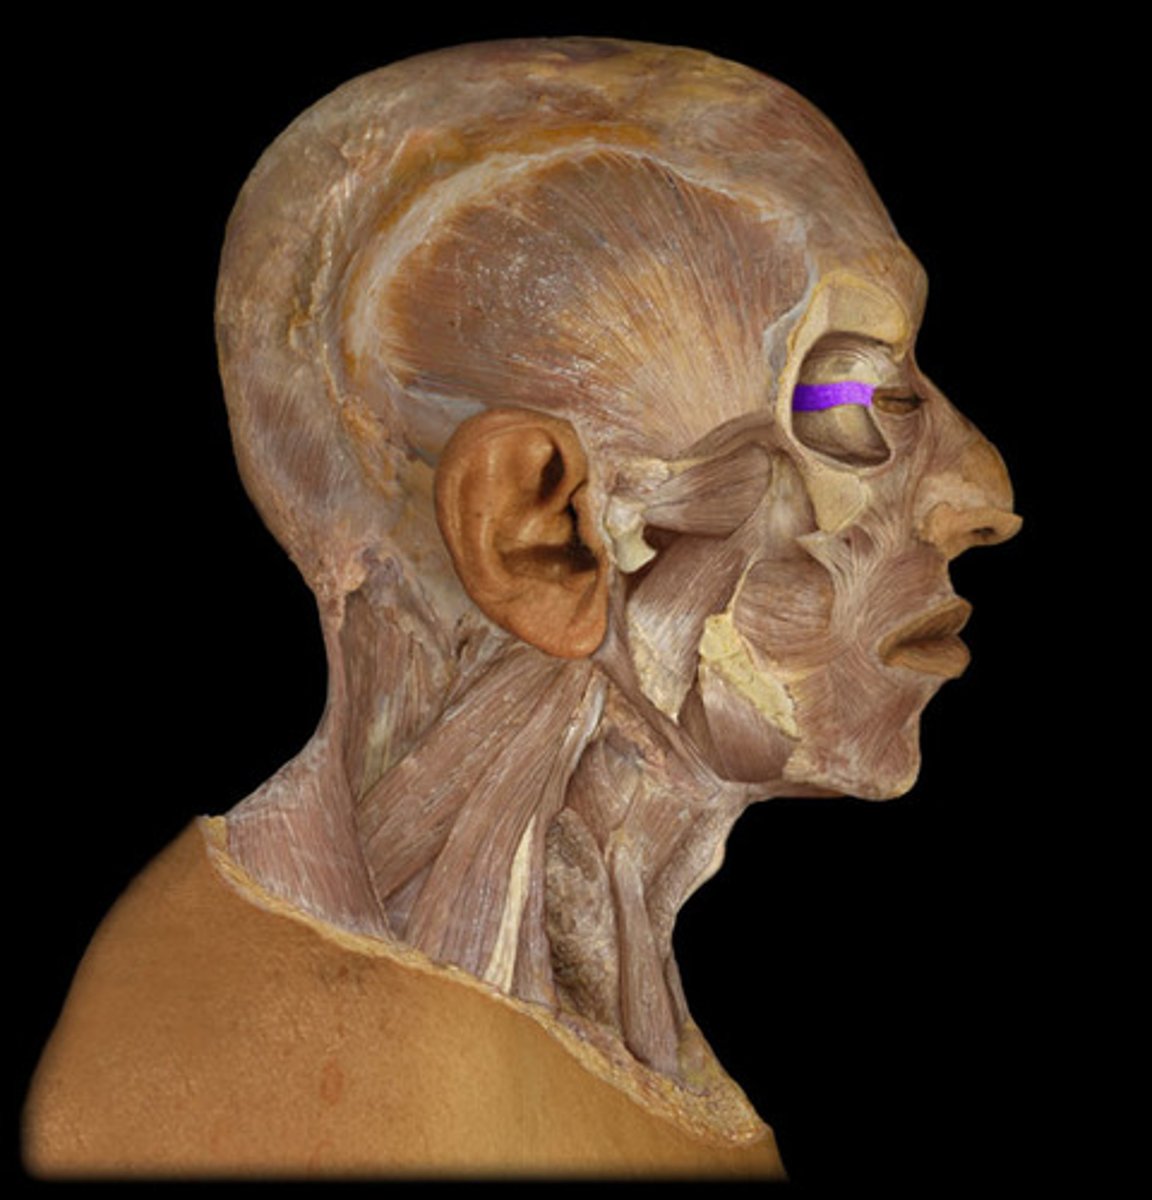

Orbicularis oculi

Levator palpebrae superioris